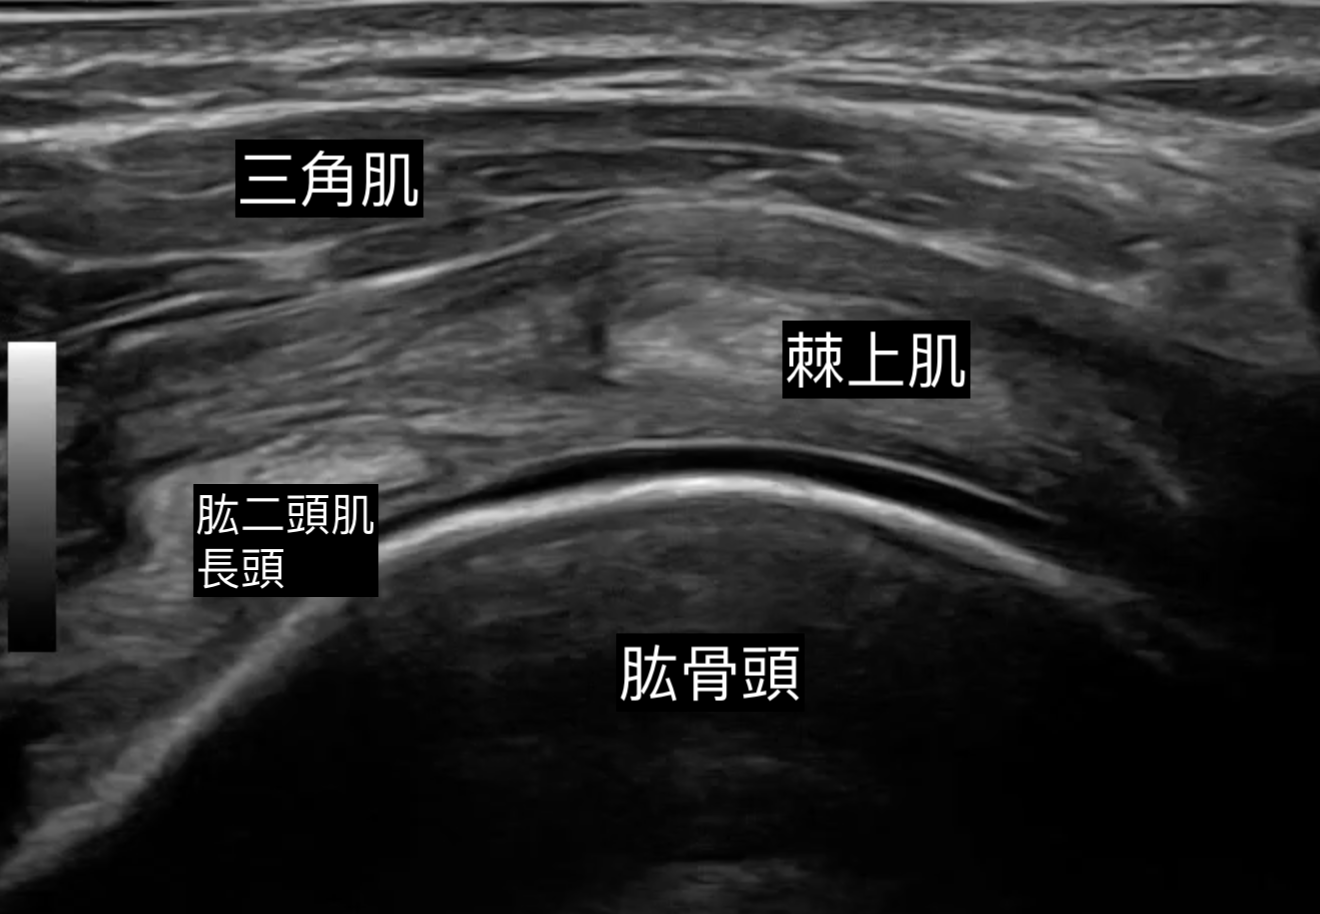

对于受五十肩困扰、一方面保守治疗效果未如理想、另一方面不希望做手术的病人,超声波介入治疗提供了一个非手术且高效的解决方案。这项程序结合了影像导航注射与关节囊松解,旨在短时间内打破僵硬关节囊的限制。